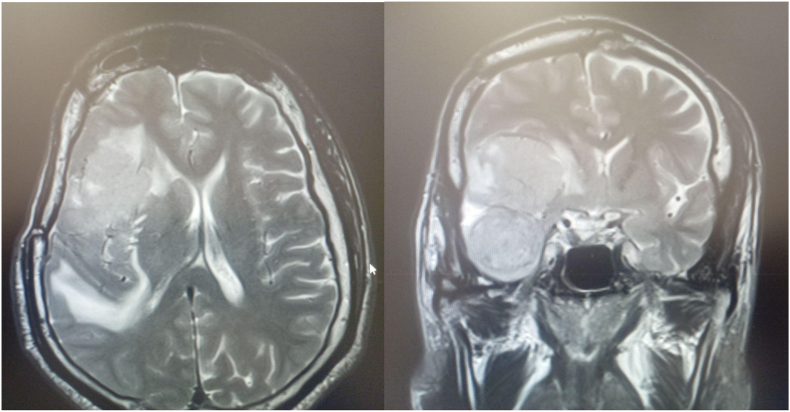

Conclusion: WHO grade II SFMs are a rare subset of supratentorial meningiomas. The most common symptom is seizure. Imaging reveals no dural tail like other typical meningioma characteristics. The cornerstone of therapy is surgery. It is necessary to assess whether such a location has a positive or negative predictive value in larger case series cohorts.